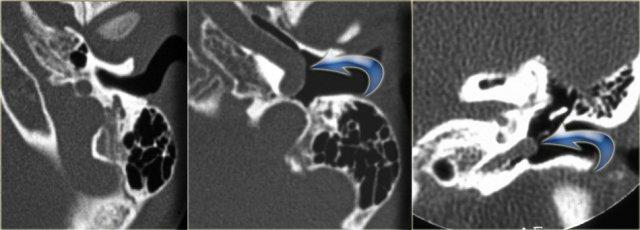

Bên trái là hình ảnh của một bệnh nhân nam 58 tuổi.

Mũi tên màu xanh chỉ cống ốc tai đi về phía ốc tai.

Hình ảnh này có thể bị nhầm lẫn với đường gãy xương (mũi tên).

Lưu ý có hình ảnh mờ đục của hòm nhĩ và các tế bào khí xương chũm.